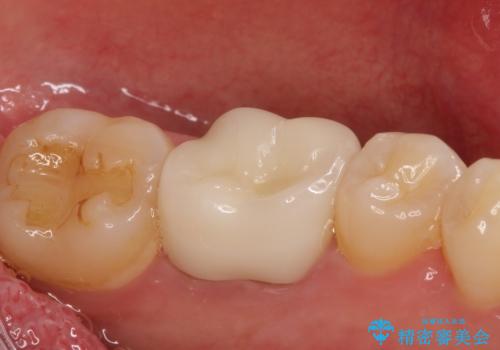

銀歯を除去し、セラミッククラウンに替えました。

審美性が良くなるだけでなく、拡大鏡を使用した治療、精度の高い材料の使用によって、虫歯の再発リスクを減らすことができます。